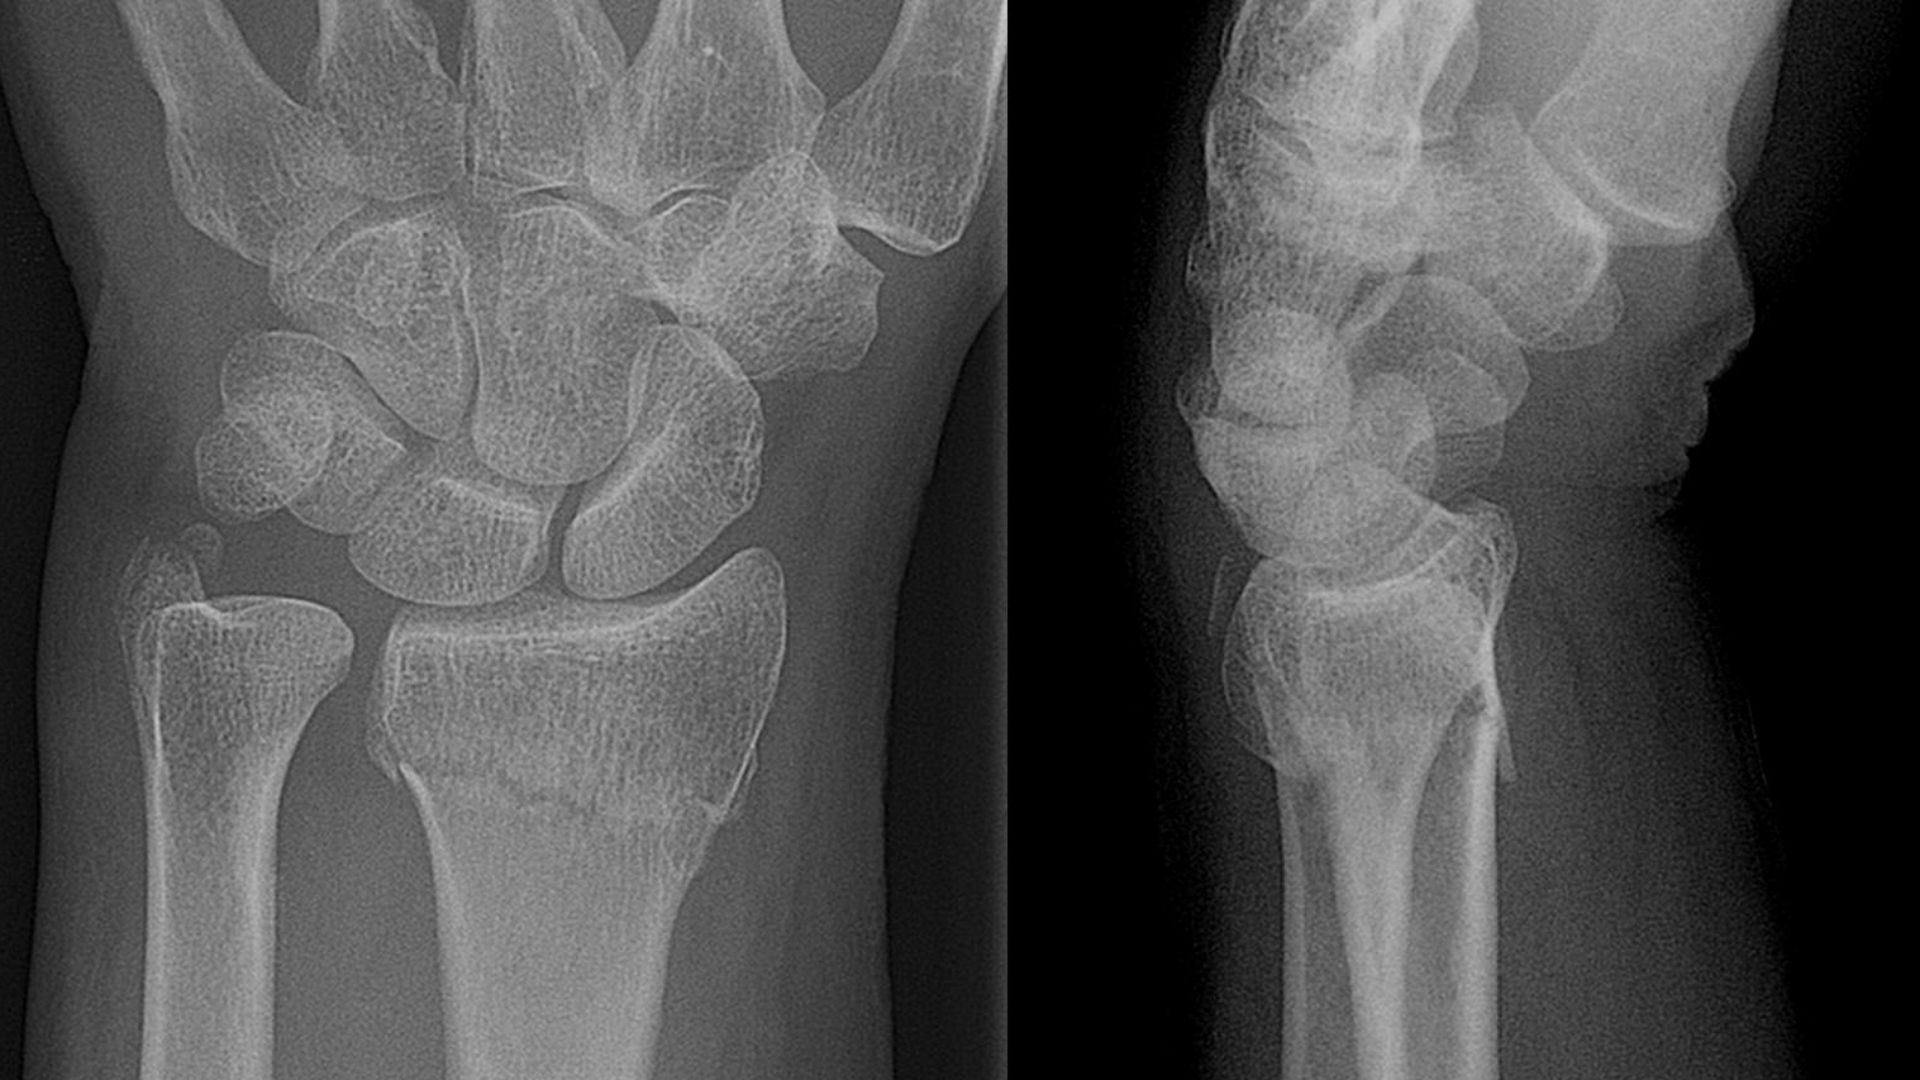

Bones Are Living Tissue

Lucien Monfils, Wikimedia Commons